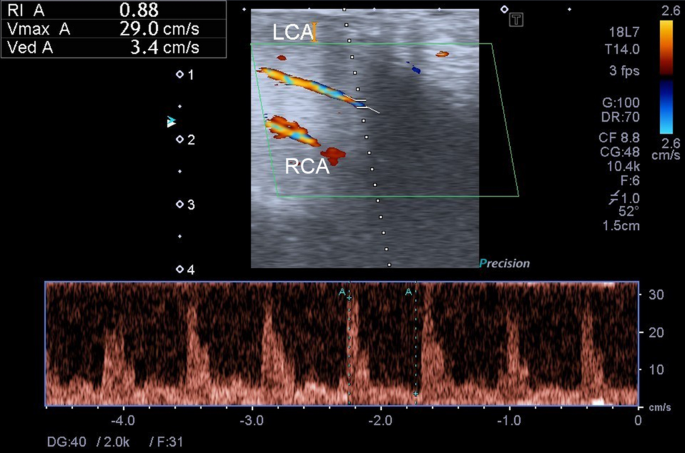

Dynamic duplex sonography

DUS was performed with a high-resolution solid-state linear array ultrasound transducer with a real-time image colour Doppler ultrasound scanner (7.5–12 MHz frequency) by an experienced andrologist (Fig. 2). An intracavernous injection of alprostadil (20 μg) was administered 10 min before the DUS exam, and the ultrasound transducer was placed over the penile root for continuous measurement of the cavernous artery3,35. The EHS was objectively observed by the andrologist during the artificial erection. EHS 1 indicated that the penis was enlarged but not hard; EHS 2 indicated that the penis was hard but not hard enough for penetration; EHS 3 indicated that the penis was hard enough for penetration but not completely hard; EHS 4 indicated that the penis was completely hard and fully rigid36. In this study, EHS < 3 was defined as the cut-off value in the ROC analysis. A PSV > 30 cm/s, an EDV < 3 cm/s, and an RI > 0.8 were considered normal10,37. Because the penis was supplied by the bilateral cavernous arteries, PSV of both sides was considered in the analyses. Therefore, we used the mean PSV of the bilateral cavernous arteries for the analyses rather than the higher or lower PSV measured from the right or left arteries. Correlation and ROC analyses from the lower PSV, higher PSV, and mean PSV of both sides were performed (Supplementary Table S2 and Supplementary Fig. S1).

An example of dynamic duplex sonography of the penis. Both LCA and RCA are shown in this sonography. The hemodynamic parameters of the LCA are measured. The PSV (shown as Vmax A) is 29.0 cm/s, the EDV (shown as Ved A) is 3.4 cm/s, and the RI (shown as RI A) is 0.88. EDV: end-diastolic velocity, LCA: left cavernous artery, PSV: peak systolic velocity, RCA: right cavernous artery, RI: resistance index.